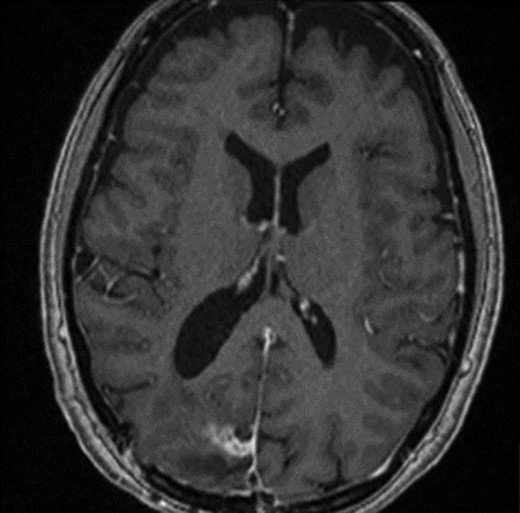

The operation was successful with a post-operative MRI within 48 h demonstrating complete resection of the tumour and resolution of the cystic lesions, but persisting intraparenchymal oedema (Fig. 3). The patient had an uncomplicated two-day stay in a neurosurgery high dependency unit postoperatively before being stepped down to the general neurosurgery ward. She was reviewed by the microbiology team and worked up for the source of infection. Blood cultures, urine cultures, CXR and transthoracic echocardiography were all negative for a source of infection. Intra-operative pus cultures isolated MSSA. The histopathology of the tumour was Meningioma WHO Grade 1 with large areas of necrosis and secondary abscess formation. She was discharged feeling well 5 days later after a satisfactory biochemical and clinical response. She was given a weaning course of steroids and a 6-week course of intravenous ceftriaxone via a PICC line as an outpatient as per microbiology advice. Ophthalmology assessment 3 months after discharge confirmed a left inferior quadrantonopia and preserved visual acuity. Repeat MRI and clinic review 8 weeks later showed no radiological residual tumour or oedema (Fig. 4), and the patient’s limb function recovered completely but had ongoing visual symptoms.

T1 weighted axial MRI postgadolinium enhancement within 48 h post-operatively. Small amount of enhancement within the surgical bed remains. Good resection margins with vasogenic oedema. This may represent a small residual. The rim-enhancing cystic lesions appear to have resolved.

T1 weighted axial MRI post-gadolinium enhancement 8 weeks postdischarge. Right occipital postsurgical appearances are again demonstrated with reduction in the extent of vasogenic oedema. The enhancing rim that was present previously has retracted, with only focal curvilinear enhancement now evident in the right occipital lobe. These appearances are likely postsurgical/treatment related, and there is no convincing residual or recurrent disease.